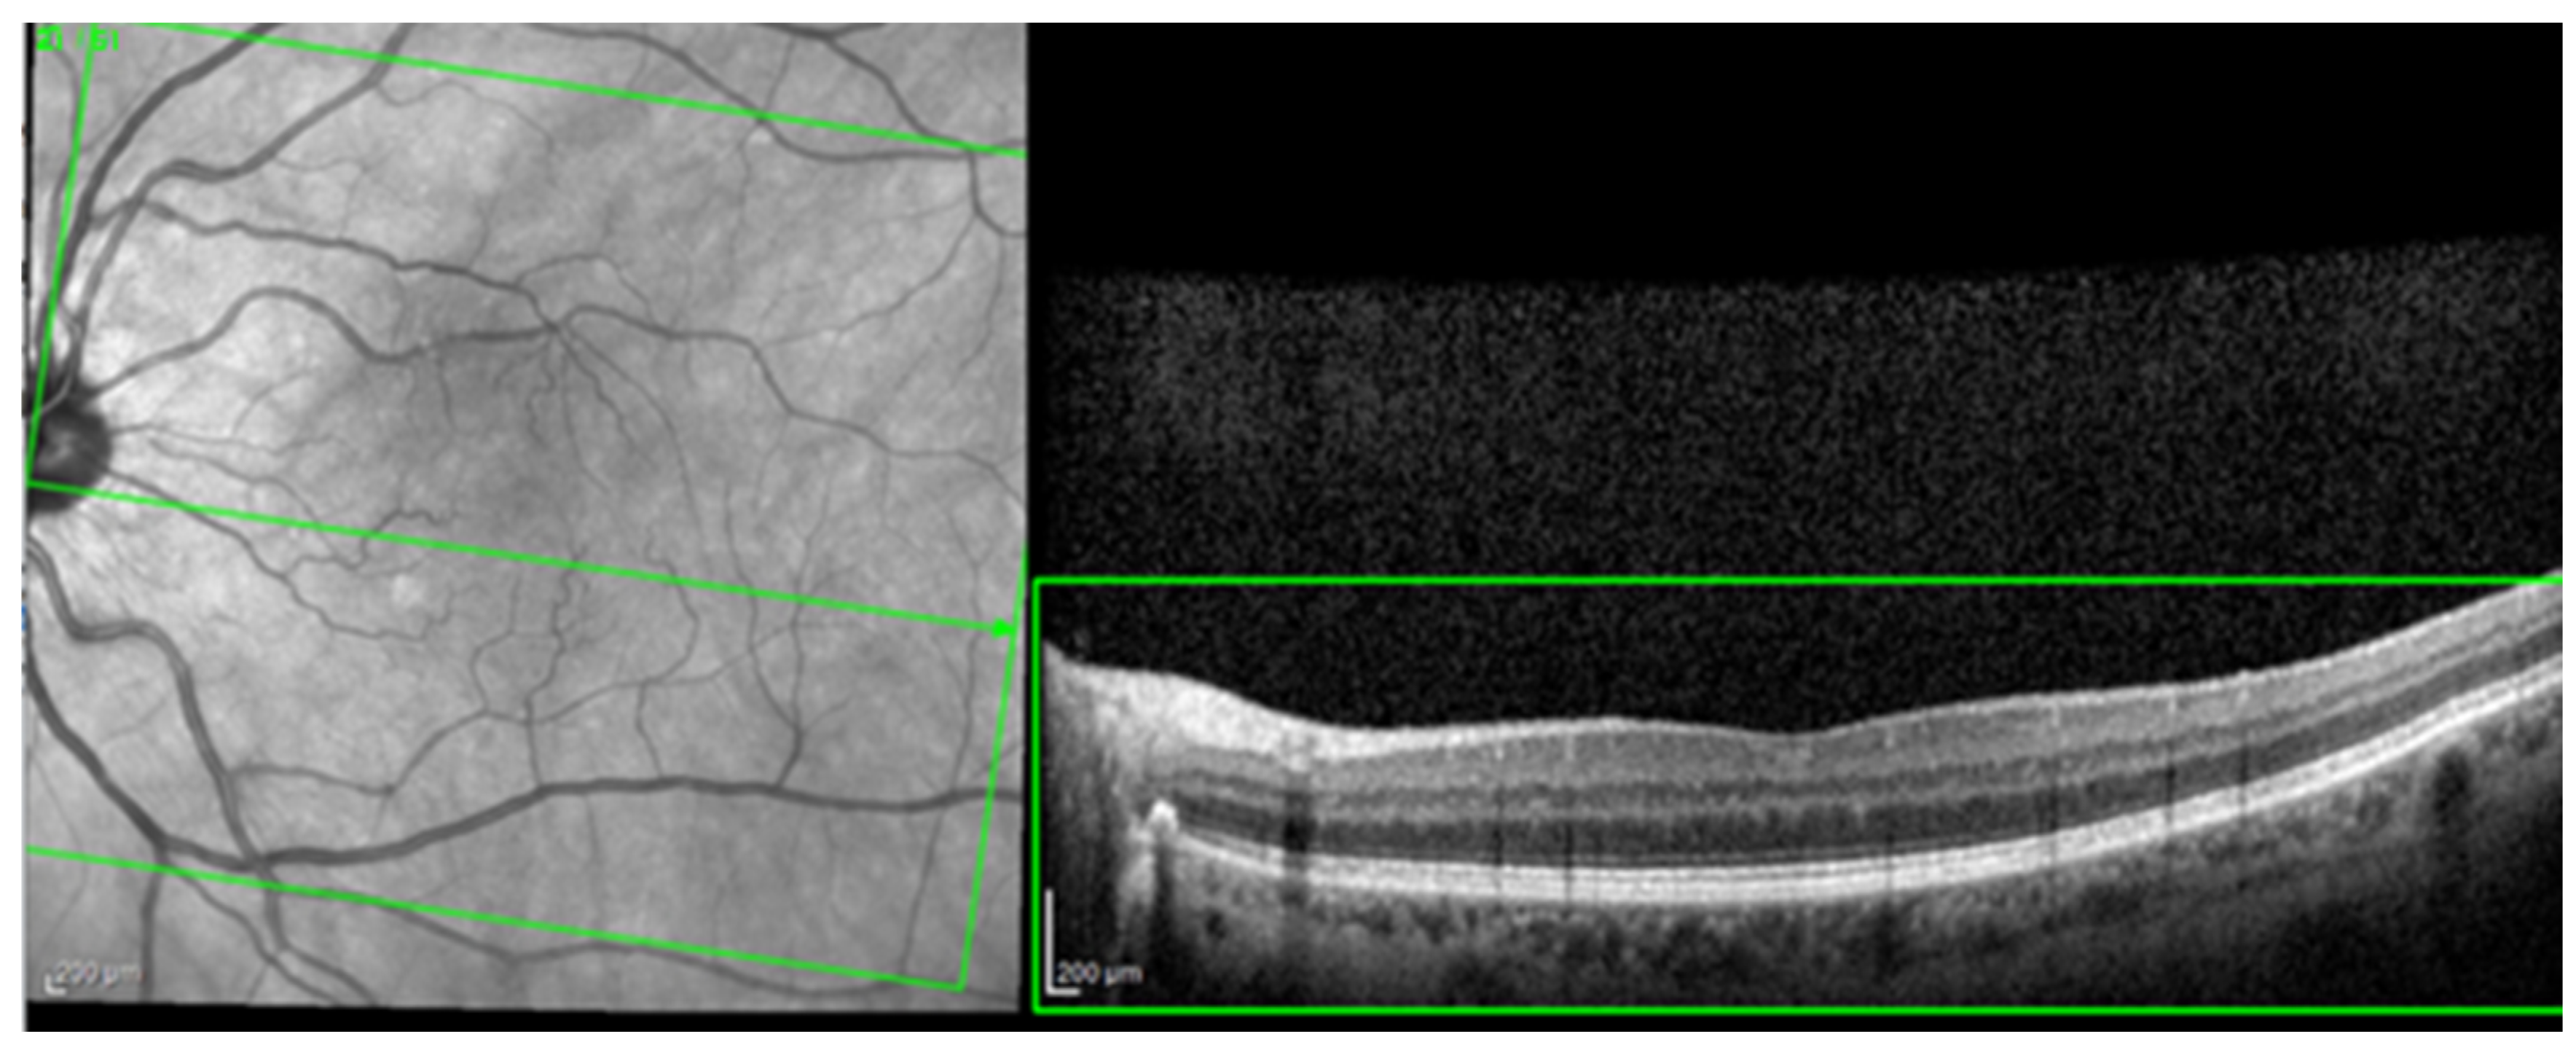

For the AI interface input, from the original OCT image acquisitions, a region of interest (ROI) was cut and standardized at a resolution of 256 × 256 pixels in order to have comparable input data for the software algorithm (see Figure 1).

Figure 1.

The selection of a region of interest (ROI) from an original optical coherence tomography (OCT) image (green box).